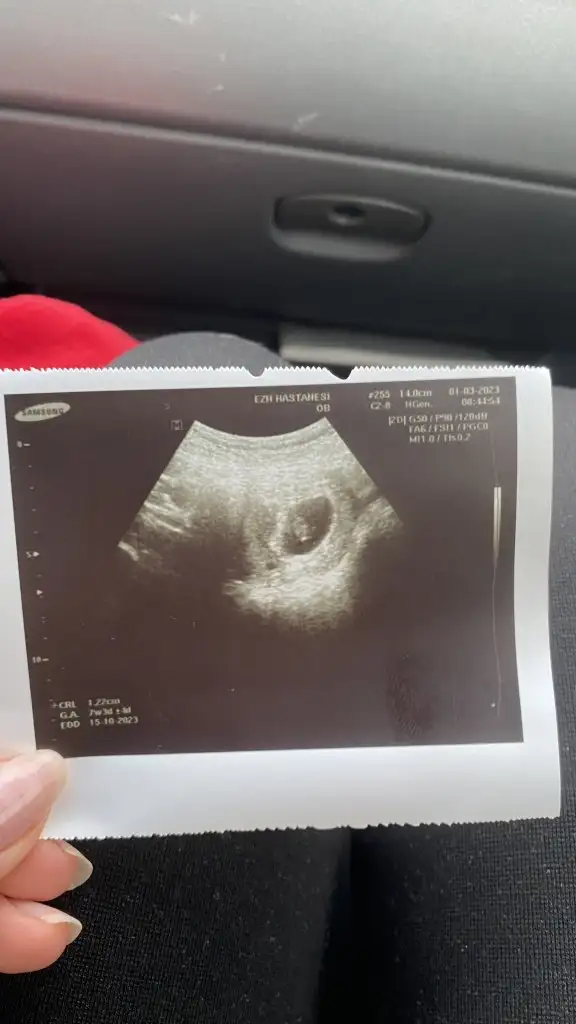

Arkadaşlar merhabalar ben yemi katıldım aranıza 6 haftalık hamileyim bugün keseyi gördük tüp bebek sonucu oldu çok şükür. Tüp benek merkezinde kalp atışını duyduktan sonra doğum vs ve kontrollerim için bir hastane ve doktor bulmam gerekiyor. İstanbuldayım Avrupa yakasında oturuyorum Anadolu da olur aslında maltepe Kartal vs önerebileceğinşz doktor hastane var mı yardımınıza ihtiyacım var

Herkese merhaba anlayan biri varsa benim ulturasonu da yorumlayabilir mi acaba 9 + 4 teyim